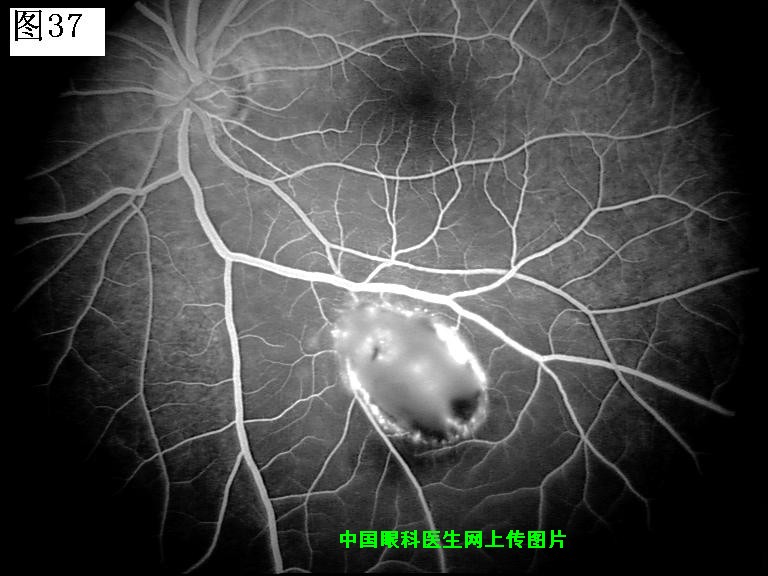

37 38 39 40